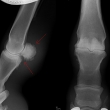

Těžká artróza ve spěnkovém kloubu

rentgenologické vyšetření